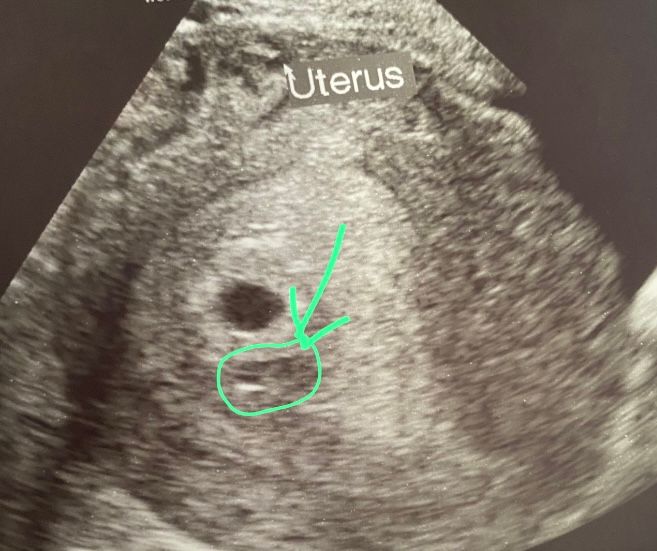

что это может быть?узи до 5 недель.

Здравствуйте по женской линии, у каждой девушки должна была быть многоплодная беременность в 4 поколениях, но не рисковали они рожать.Все надеюсь и жду что меня тоже ждёт это. Сейчас беременность до 5 недель . Может ли точка под плодным яйцом быть , вторым малышом?🙏❤️ Или стоит ли вообще обращать на это внимание?

Не похоже на пя эта точка